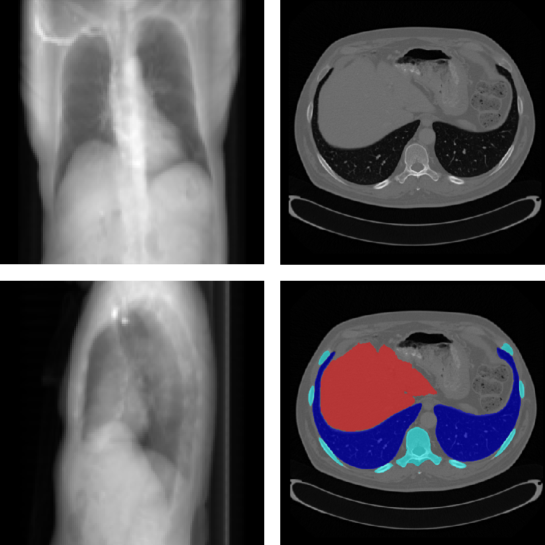

Datasets

For the pre-training of the ϕssubscriptitalic-ϕ𝑠\phi_{s}, we select a public dataset of CT volumes with voxel-wise annotation of abdominal organs, namely CT-ORG dataset [21]. The CT-ORG dataset consists of 140 throat-abdominal CT scans with annotated lungs, bones, liver, bladder and brain, with voxel size ranging from 0.56 mm to 1.0 mm in vertical direction. Because the reconstruction dataset covers only chest region, the annotations of lungs, liver and bone in the CT-ORG dataset are used in the following experiments. Some samples from the datasets are shown in Figure 8. All CT volumes in the LIDC-IDRI dataset and the CT-ORG dataset are resampled to a uniform voxel size of 1 mm by 1 mm by 1 mm to ensure the consistency during model training. 812 CT images from the LIDC-IDRI dataset are used during the model training and 214 images for test. For training the ϕssubscriptitalic-ϕ𝑠\phi_{s}, 112 CT scans are used for training and 28 images for test. The X-ray projections are simulated in a way to mimic the fan-beam CT forward projection, by using the aforementioned scanner geometry. The CT volumes are first resampled to voxel size of 2.5 mm in each direction and then clipped to the uniform volume/image size of 128. The resolution of the input X-ray projections is also 128. For the GAN training, both X-ray projections and the CT volumes are normalized to 0.0 to 1.0 using the same parameters.

Refer to caption

Figure 8: Example simulated X-ray projections from the LIDC-IDRI dataset and fan-beam geometry (left) and one slice from the CT volume with organ segmentation from CT-ORG dataset (right).